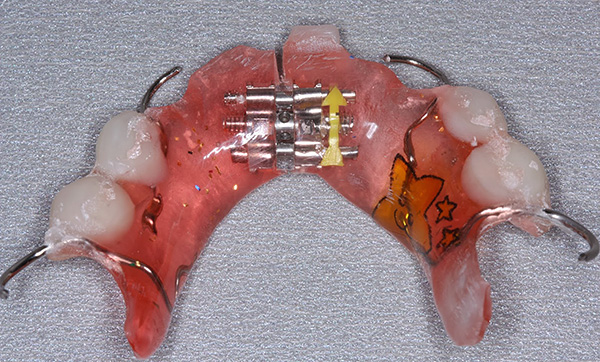

Para crianças muito pequenas, um ortodontista pode oferecer um boné ortodôntico transparente (tênis) - para preservar o espaço disponível na dentição após a perda de um dente ou dentes.

Em seguida, a bandeja é substituída por um aparelho de placa com um parafuso de expansão e dentes artificiais que substituem um defeito na linha. Um exemplo é mostrado na foto abaixo: